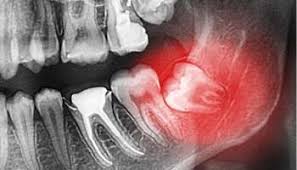

Why are wisdom teeth removed? They may refer you to an oral surgeon, who will do the procedure in their office. Additional costs of wisdom tooth removal. With a comprehensive dental plan, you can dramatically reduce what you're required to pay out of pocket. How much you can expect to pay out of pocket for wisdom teeth removal, including what people paid.

How much does it cost to have wisdom teeth removed? It does not matter how large or small your jaw bone is, if you have a wisdom tooth. Almost all dental insurance schemes cover up to 40 to 60 percent of the total cost of removing the cost of extracting a wisdom tooth depends on the condition of the tooth and standard dental charges existing in a region or city. How can you tell if wisdom teeth are impacted or infected? Your wisdom teeth are the only teeth you grow as you enter your late teens or early twenties. In some cases if your dentist believes that your wisdom teeth aren't growing in correctly, he may suggest having them removed even before they become a problem. The question is, how much is that the good news is that most dentist's offices do offer some type of financing when it comes to things that cost this much. In most cases, wisdom teeth are removed before they erupt.

Signs that it's time to remove your wisdom teeth.